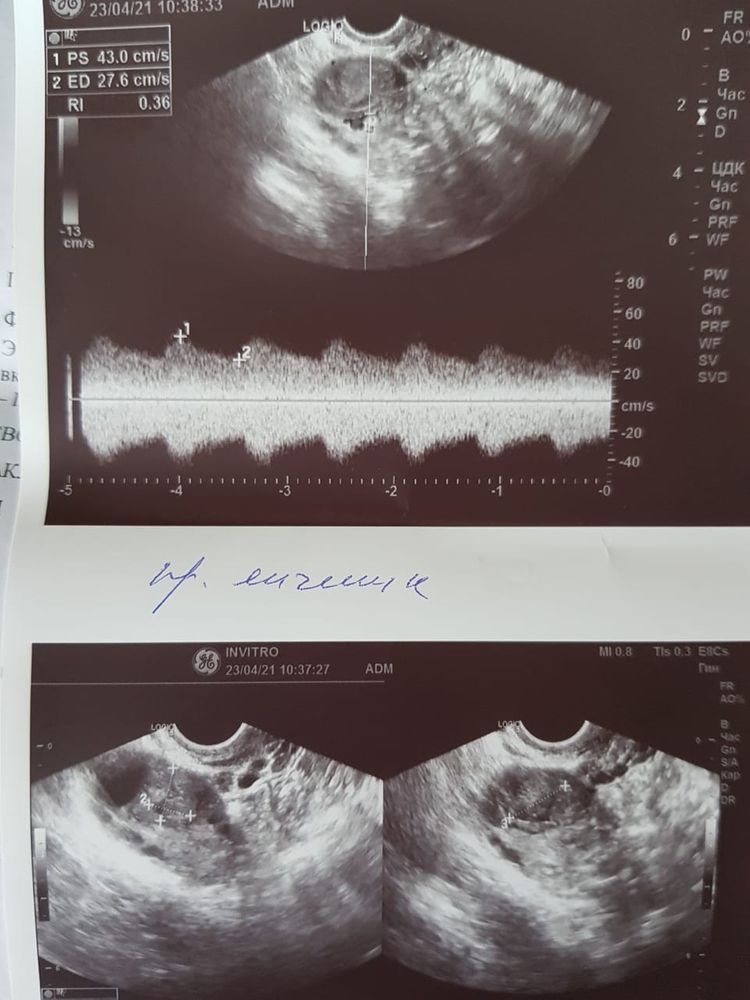

ФолликулометрияВ правом яичнике намерили ДФ 20мм (20x17x23) и ЖТ 14x11x17 с кровотоком.